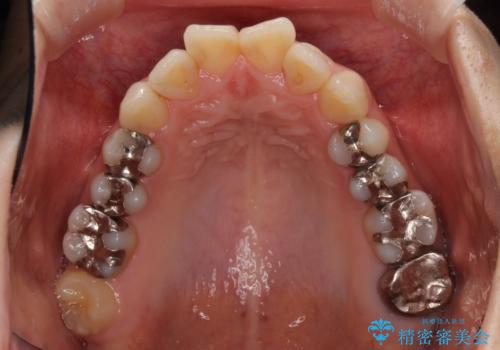

- 上下のデコボコと奥歯の咬みにくさを気にして来院された患者様です。

上顎骨の幅が下顎骨よりも小さいので、拡大装置により骨幅を広げて上下関係を改善し、その後インビザラインにて歯並びを整えることとしました。